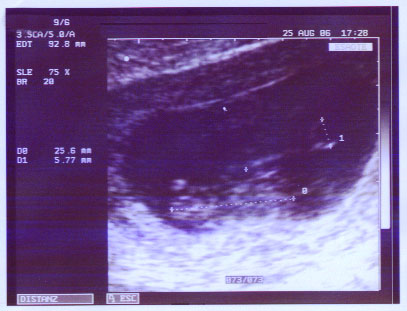

Schon 8 mm groß!

Knapp 26 mm - in anderthalb Wochen um das dreifache gewachsen - Wahnsinn!